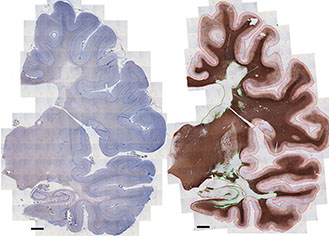

Examples of two MS brain slices stained to show different compounds